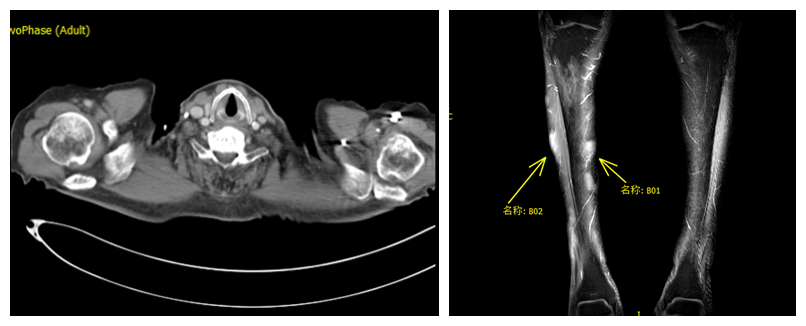

定期随访:PTE-CT(2022-08-13)提示病灶消失,达到完全缓解。

图8. PET-CT(2022-08-13 vs 2022-02-25)提示病灶消失,达到完全缓解